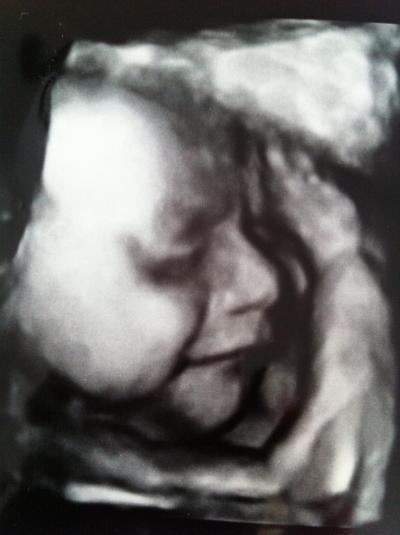

CTG war alles in Ordnung, hatte eine Miniwehe, die ich selbst garnicht gespührt habe. Herztöne waren super. Bei der VU ist leider festgestellt worden, dass mein Gebärmutterhals zu kurz ist, von 4,6 cm auf 3,2 cm. Ich soll mich schonen und er hat mir Magnesium verschrieben. Jetzt muss ich am Dienstag direkt nocheinmal zur Kontrolle.... 3D war diesmal nach dem 3. Versuch spitze, hänge mal ein Bild von unserer kleinen lächelnden Prinzessin dran

Bild zu Gestern CTG/VU/3D Ultraschall - Forum für August - Mamis

Wow. Dein Doc hat aber einen super 3D-US. Das sieht ja fast aus wie ein Foto!!! Süß!